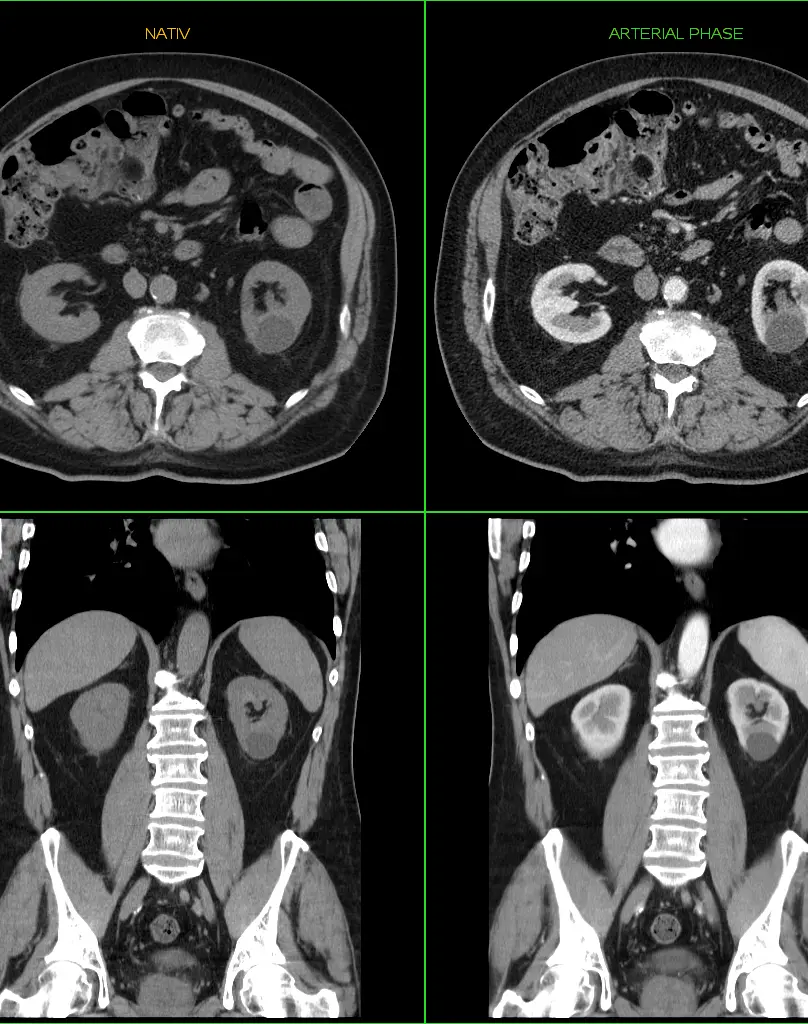

Контрастное усиление (за 1 зону)

Это методика улучшения визуализации тканей и сосудов с помощью внутривенного введения специального вещества, усиливающего контрастность изображений. Чаще всего применяются препараты на основе гадолиния (редкоземельных металлов), которые безопасны и хорошо переносятся пациентами.